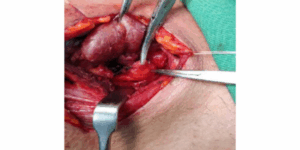

Oral Cancer

Tongue-cancer